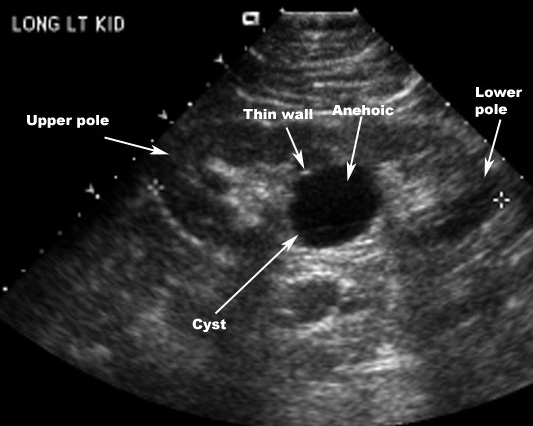

Ultrasound characteristics: